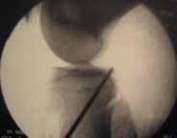

9. The PCL guide is set, and its position is confirmed with fluoroscopy and arthroscopy (

TECH FIG 2B

).

10. A guidewire is drilled to but not through the posterior cortex.

1. Fluoroscopy is used to confirm the path of the guidewire (

TECH FIG 2C,D

11. With the 30-degree arthroscope in the posteromedial portal, the PCL curette is introduced through the anteromedial portal and is used to protect the posterior knee

---

A B C

TECH FIG 2 • A. Posterior cruciate ligament (PCL) drill guide positioned to facilitate guide pin exit at the PCL insertion. B. Once the PCL drill guide is set, it is confirmed arthroscopically and fluoroscopically. C. The tibial guidewire is drilled under fluoro- D scopic guidance. D. The tibial guidewire position is confimed with fluoroscopy. structures as the guidewire is carefully advanced through the posterior cortex under arthroscopic visualization.